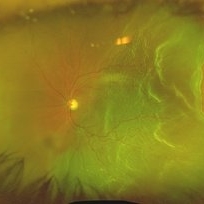

Secondary Pigmentary Degeneration of Retina

Secondary Pigmentary Degeneration of Retina

Jul 18 2025 by Kimberly Wakester

Optomap RGB and AF of an 63-year-old man with secondary pigmentary degeneration of the retina. Patient's Spark genetic testing revealed heterozygous mutations of unknown significance in LRP5, COL18A1, CPLANE1, SLC24A1 and VCAN. Clinical findings most consistent with Wagner's Syndrome (VCAN mutation, autosomal dominant). Will continue follow up care every 6 months with dilated exam and repeat OCT and Optos imaging.

Photographer: Kimberly Wakester, COA, OCT-C

Imaging device: Optos California

Condition/keywords: secondary pigmentary degeneration, Wagner's Syndrome